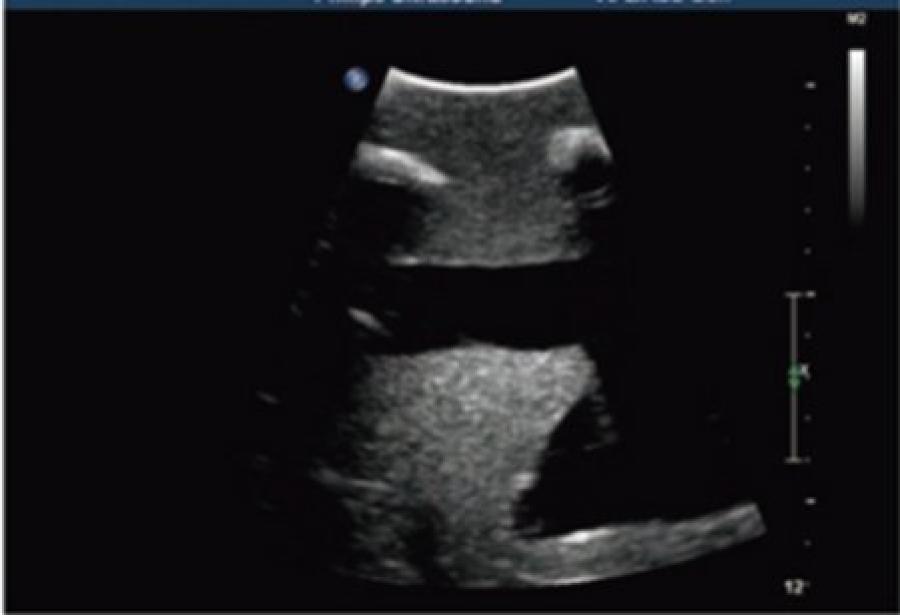

Simulatore ecografabile per addestramento alle tecniche di toracentesi e toracostomia sotto guida ecografica

– ActFast LLC Progettato per offrire un'esperienza formativa realistica e altamente efficace, il simulatore ecografabile di ActFast LLC rappresenta una soluzione avanzata per l'addestramento alle tecniche di toracentesi e toracostomia sotto guida ecografica. Realizzato con materiali che replicano fedelmente le proprietà acustiche e la densità dei tessuti umani, questo modello consente un imaging a ultrasuoni preciso e affidabile. Il simulatore riproduce in modo dettagliato l'anatomia del torace umano, includendo: Pelle e tessuto sottocutaneo Parete toracica con costole (quinta, sesta, settima, ottava e nona) Spazi intercostali Polmoni, cavità pleurica e versamento pleurico Diaframma e milza Il lato sinistro del torace presenta strutture polmonari normali, mentre il lato destro è configurato con pneumotorace e versamento pleurico. È possibile infondere quantità variabili di gas o liquido nella cavità pleurica per simulare diverse condizioni cliniche. Il modello supporta l'esecuzione di: Puntura del pneumotorace sulla linea medioclavicolare destra al 2° spazio intercostale, sotto guida ecografica o tramite punti di riferimento anatomici superficiali Aspirazione del versamento pleurico sulla linea ascellare anteriore destra al 5° spazio intercostale, sulla linea ascellare media al 6° e 7°, e sulla linea scapolare all'8° e 9° spazio intercostale Cateterismo e drenaggio toracico con possibilità di lasciare in sede un tubo per la gestione postoperatoria e il controllo di eventuali ostruzioni Il simulatore è dotato di un tubo di riempimento per il reintegro del liquido pleurico e di una pompa manuale per il gonfiaggio del gas pleurico, offrendo così una simulazione completa e ripetibile delle condizioni cliniche. Ideale per la formazione di medici e personale infermieristico, questo strumento didattico permette di acquisire competenze pratiche fondamentali in un ambiente sicuro e controllato, migliorando l'efficacia dell'intervento clinico reale.